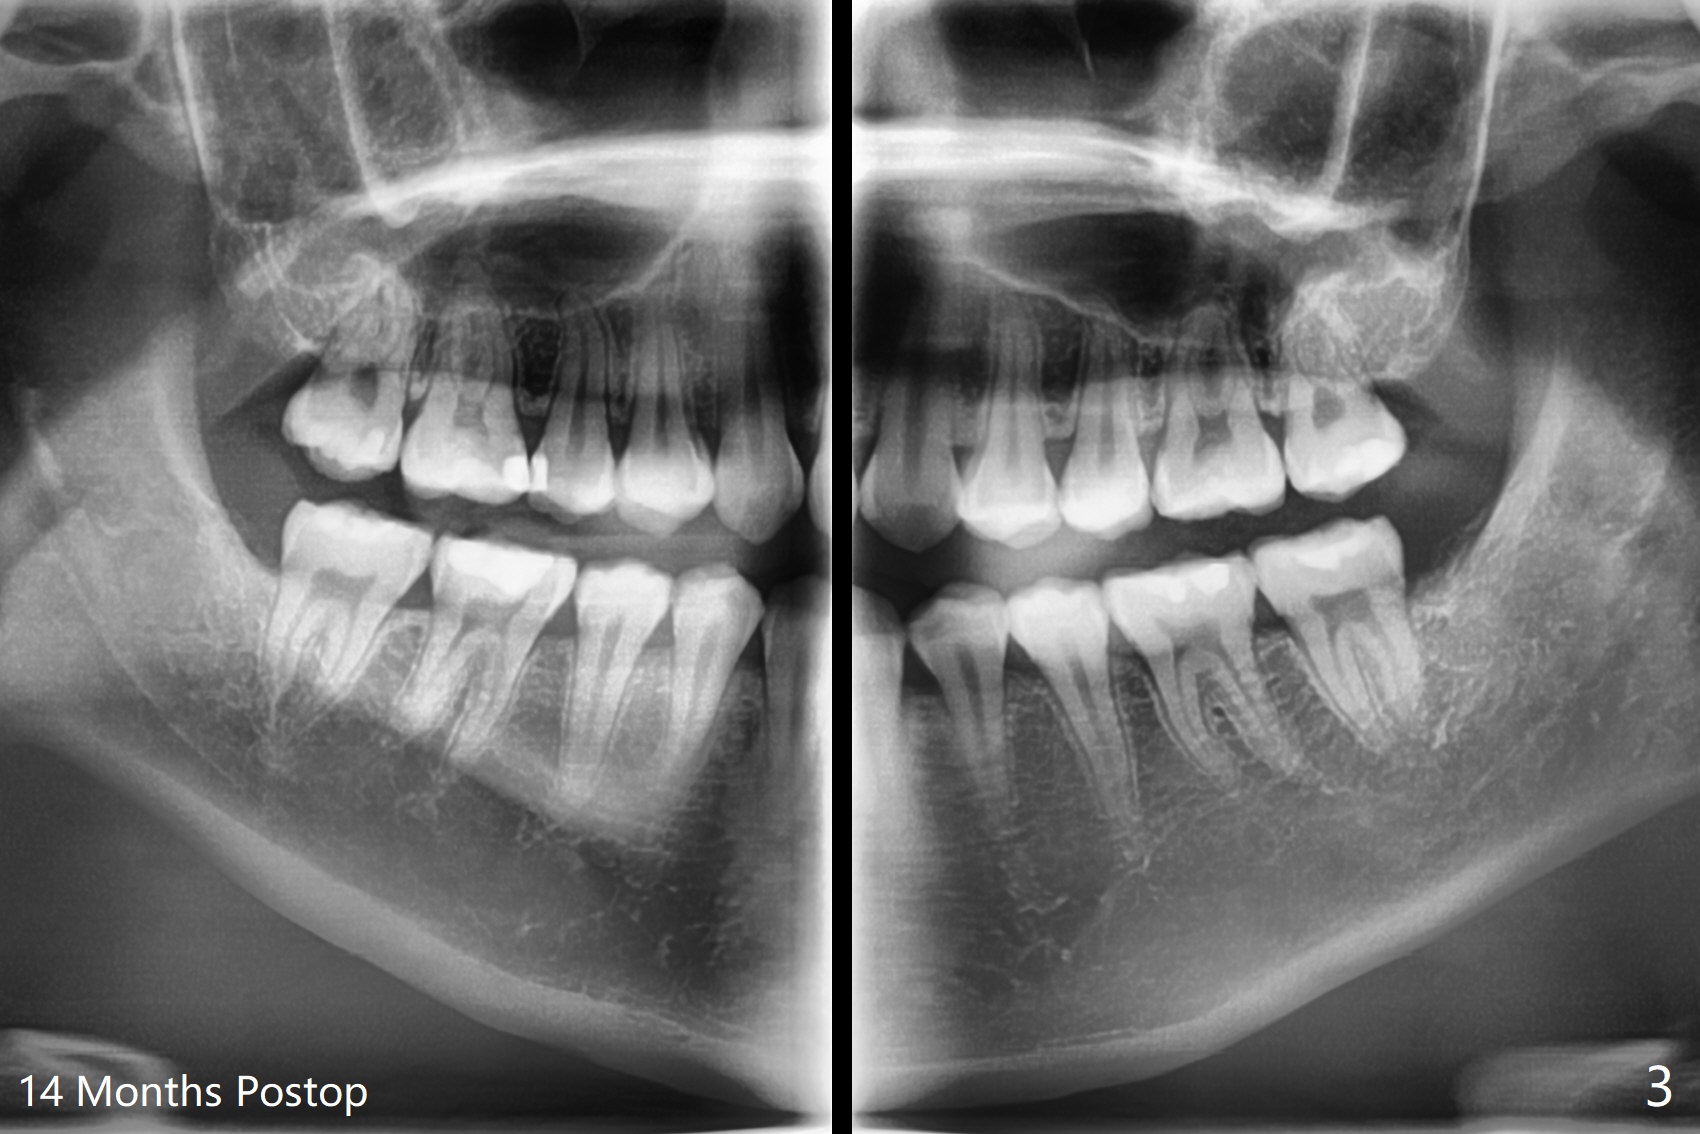

A 19-year-old woman requests extraction of #1,16,17 and 32 (Fig.1). The surgery is smooth except the fact that a surgical fissure bur tip is found to have been fractured without trace at #17. Before placement of Osteogen plug (Fig.2 O) and suture at #17, a regional panoramic X-ray for bitewing is taken. All of the sockets heal in 14 months (Fgi.3).